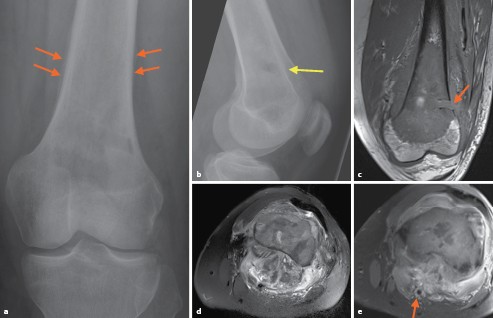

Osteolytische Diaphysare Tibialasion Bei Zunehmendem Dumpfem Dauerschmerz Uber Dem Schienbein Springerlink